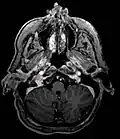

Glomus jugulare tumor -

Ectopic functional paraganglioma (glomus jugulare) in a patient with VHL. T2 weighted MRI at the same location demonstrates a high signal mass consistent with a paraganglioma. Extra adrenal paragangliomas can be found in VHL (arrow). -